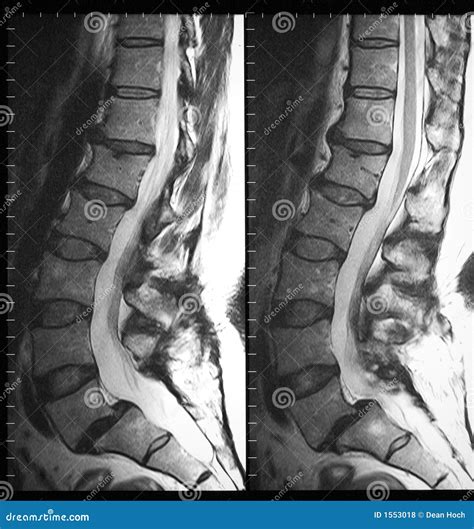

The lumbar spine is the lower section of your back, consisting of five vertebrae (labeled L1 through L5). This region supports the majority of your body weight and facilitates movement, making it highly susceptible to wear and tear, injury, and structural issues. A lumbar spine MRI uses strong magnetic fields and radio waves to create high-resolution images of the bones, intervertebral discs, spinal cord, nerve roots, and surrounding soft tissues.

Unlike an X-ray or CT scan, which are excellent for viewing bone density and fractures, an MRI excels at highlighting soft tissue abnormalities. It can detect subtle changes in disc hydration, identify inflammation, and reveal precisely where nerves may be compressed by bulging or herniated discs.

Once the scan is complete, the images are sent to a radiologist, a physician who specializes in interpreting diagnostic imaging. They will prepare a report detailing their findings and send it to the doctor who ordered the test. It is common to see medical terminology in these reports, such as "annular tear," "facet hypertrophy," or "neural foraminal narrowing."

It is important not to panic if you read words that sound alarming. Many age-related changes, such as mild disc bulging or minor arthritis, are commonly found even in people who have no back pain. Your physician will correlate the findings of the lumbar spine MRI with your physical symptoms and clinical examination to determine the most effective treatment plan, which may range from physical therapy and epidural steroid injections to surgical intervention.

- lumbar spine mri images

- lumbar spine mri anatomy